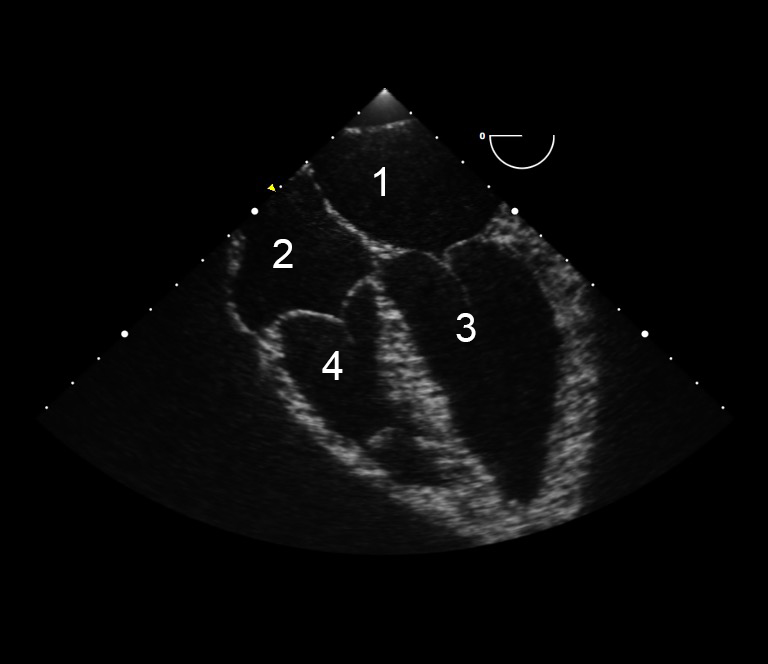

TEE Resus Mid-esophageal 4 Chamber 2 IU Image Left Atrium Right Atrium Left Ventricle Right Ventricle